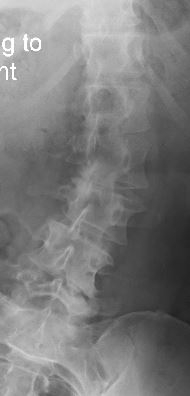

i am the bionic woman, iron woman, titanium broad, i don't know quite yet hopefully i don't break any of the rods or pull any screws...but heres the before and after xrays....

before: lateral scoliosis

and rotatory scoliosis

right bending.JPG

right bending.JPG (15.55 KiB) Viewed 3022 times

i am pretty darned close to 0 degrees on the scoliosis!!!! and my spine isn't twisted anymore either! it feels totally different to walk, sit, stand, basically to do anything, but that's okay! the square things in the after xrays are cages to replace the discs that were removed.

so they removed the backs off the vertebrae at L2 L3 L4 and L5 it looks like from the xrays. took out all the facet joints (the bars are where they would be)....so that freed up all the pinched nerve roots and took the pressure off my spinal cord.